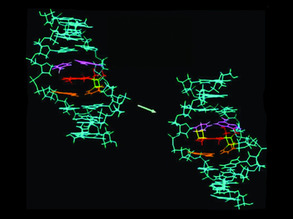

Keeping Cancer Quiet

Silence is Golden